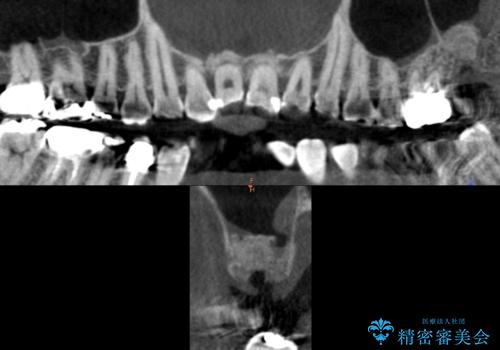

患者様のご希望により抜歯してインプラントによる治療を行いました。

上顎洞が近接しており上顎骨の厚みが薄いことから、ソケットリフト(上顎洞底挙上術)をインプラント埋入と同時に行いました。

ソケットリフトにより上顎洞底を挙上し骨造成することにより、骨の厚みが薄い部分でもインプラントが可能になります。